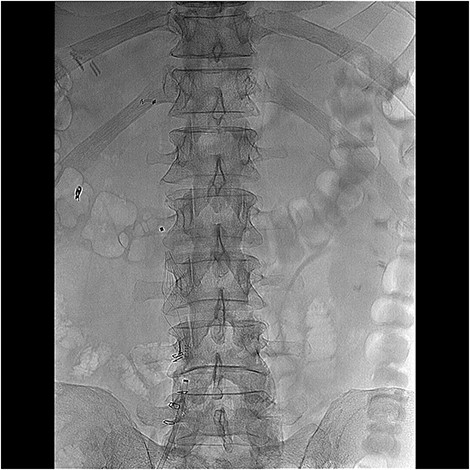

Considering the pulmonary embolism and the contraindications for anticoagulation therapy, a retrievable inferior vena cava filter type Angel (Mermaid medical, Copenhagen, Denmark) had been placed (Fig. 7). The patient had total recovery and was discharged the postoperative day 14 overall. He remains asymptomatic 6 months after.